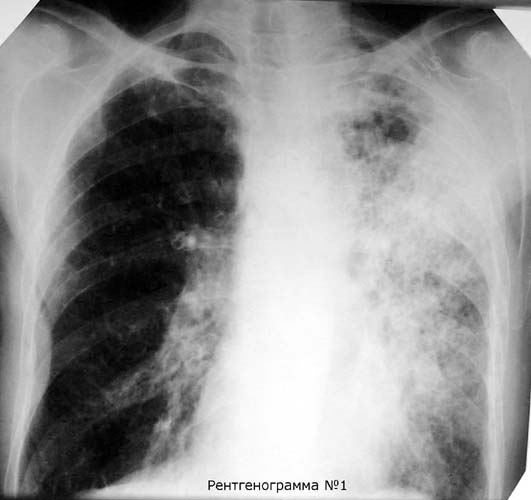

Рентгеновские снимки при пневмоцистной пневмонии